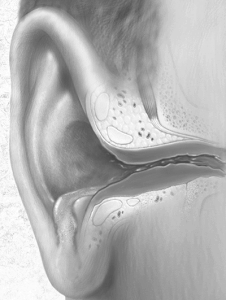

Батьки через недогляд можуть пропустити нежить або не долікувати його, що нерідко закінчується хронічною закладенням носа. Пізніше, крім помітного дискомфорту виявляється в слуховий трубці, яка з'єднує пазухи носа і середнього вуха, порушення прохідності. До того ж даний відділ вуха бере участь в відходження слизових виділень через носоглотку і нормалізації у дітей звукових сприйнять.

Пропонуючи певну терапію секреторного отиту у дітей, основну увагу приділяють корекції роботи слухової труби, в свою чергу відновлення процесу вентиляції барабанної порожнини сприяє вирівнюванню тиску і припинення того, що відбувається випоту виділень. Одночасно порожнину дренується, а скупчилася рідина починає виливатися в носоглотку.